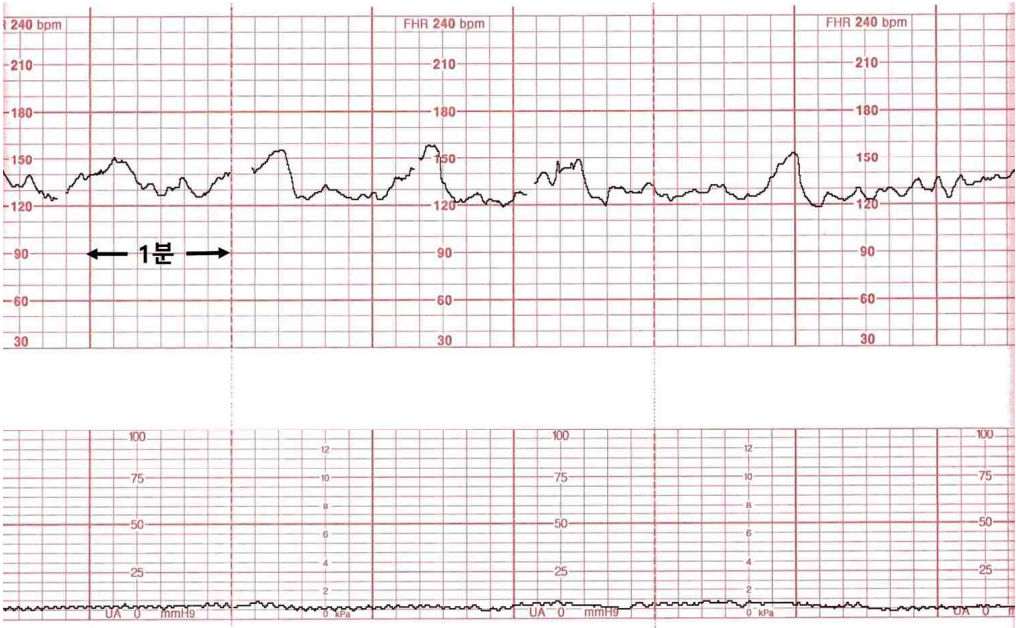

임신 42주인 33세 미분만부가 산전진찰을 받기 위해 병원에 왔다. 혈압 120/70 mmHg, 맥박 78회/분, 호흡 20회/분, 체온 36.7℃이다. 골반검사에서 자궁경부는 닫혀있다. 초음파검사에서 태아는 두위, 예측태아몸무게 3,400g (10백분위수 3,266g), 양수지수 7cm, 태반은 정상이다. 비수축검사 결과이다. 처치는?

Fetal CTG: FHR nl, no uterine contraction

• 골반검사상 자궁경부가 닫혀있으며, Fetal CTG상 자궁수축이 확인되지 않으므로 분만 진통이 시작되지 않았음을 알 수 있다.

• 비수축검사 20분 연장: NST상 20분간 반응성 소견이 없을 경우 태아를 깨운 뒤 비수축검사를 20분 더 진행해야 한다. 현재 태아는 반응성이 확인되었으므로 비수축검사를 연장할 필요는 없다.